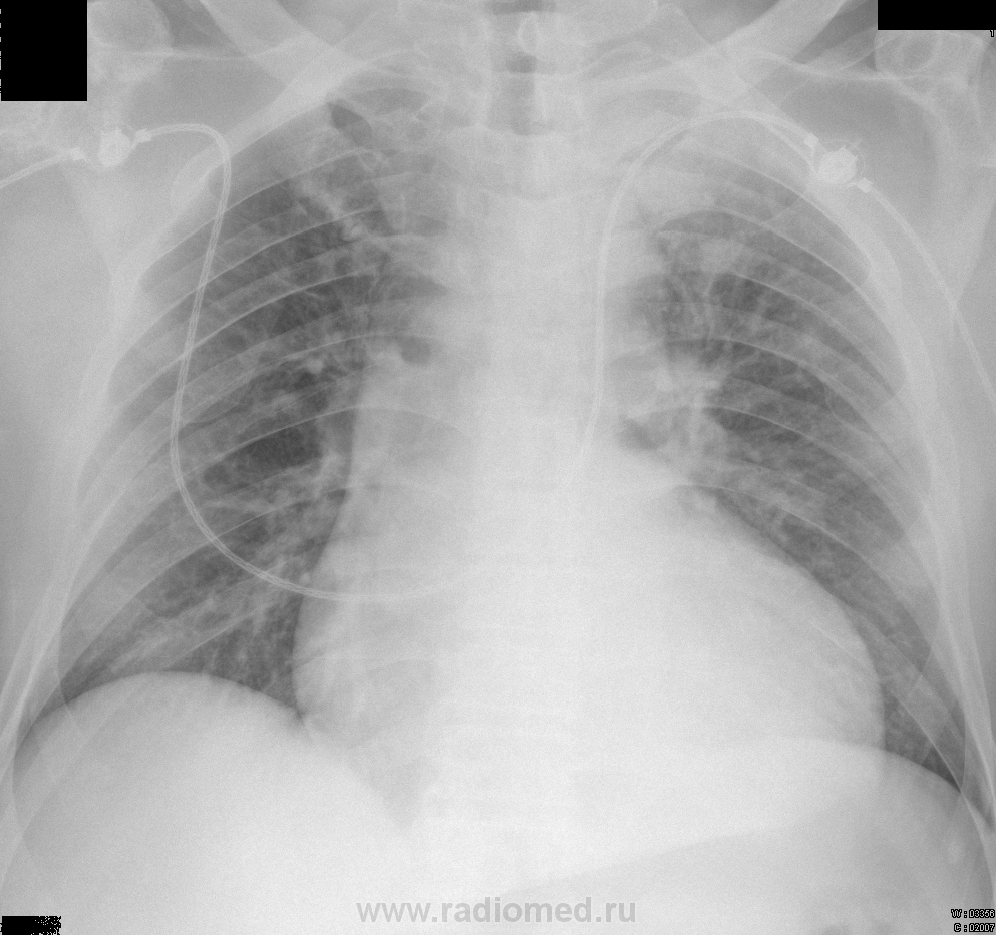

Сердце расширено и за счет правого желудочка тоже (впрочем - снят лежа). Но причина кровохарканья, на мой скромный взгляд, все же в туберкулезе. Вроде и каверны есть.

-левая верхушка-инфильтрат или старое, не имеет значения-кровь не оттуда

-мне более интересно правое легкое: уменьшено в объеме? возможно-бронхоэктазы в нижнем легочном поле? а в среднем - толстостенная полость с неровными контурами и с "дорожкой"? (Все коряво обвела, как могла :) )

Расширение границ сердца, застой в лёгких. Полости я не вижу, по моему воздушный столб трахеи смещён вправо, а прозрачность легочного поля слева на верхушке снижена. Может рак?

Справа апикально мерещится воздух (пневматоракс или правда мерещится?). Ну и сосудистый рисунок усилен, сердце увеличено. И все. Туберкулез с кавернами кажутся слегка надуманными, но у меня и опыта 0.

1005 китайское предупреждение себе самой-не делай "умных" замечаний в конце недели и вот-вот в отпуске-но... У меня складывается впечатление, что межреберные промежутки слева несколько уже, верхушка затемнена (частичный ателектаз верхней доли ?) + к этому кровь-как бы не вышло в итоге образование верхнедолевого бронха?

Легочное кровоизлияние. Бисегментарное верхнедолевое снижение пневматизации по типу матового стекла с утолщением долькового интерстиция + гидроторакс слева, лимфаденопатия парааортальных, паратрахеальных (и бронхопульмональных?) лимфоузлов. От банальной пневмонии с диапедезом эритроцитов до кровоизлияния из артерио-венозного шунта / тромбоза сегментарной верхнедолевой ветви левой ЛА. Без контрастирования - гадание на нативной гуще. Бронхоскопия в помощь. И клиника, её развитие. Имея только то, что показано, написала бы неполный инфаркт S1+2 слева под вопросом.

Дилятация левых отделов сердца

Изменения в левой верхушке.

Что-то, кроме застоя в этимх легких есть, но по снимку такого качества, сказать точнее сложновато.